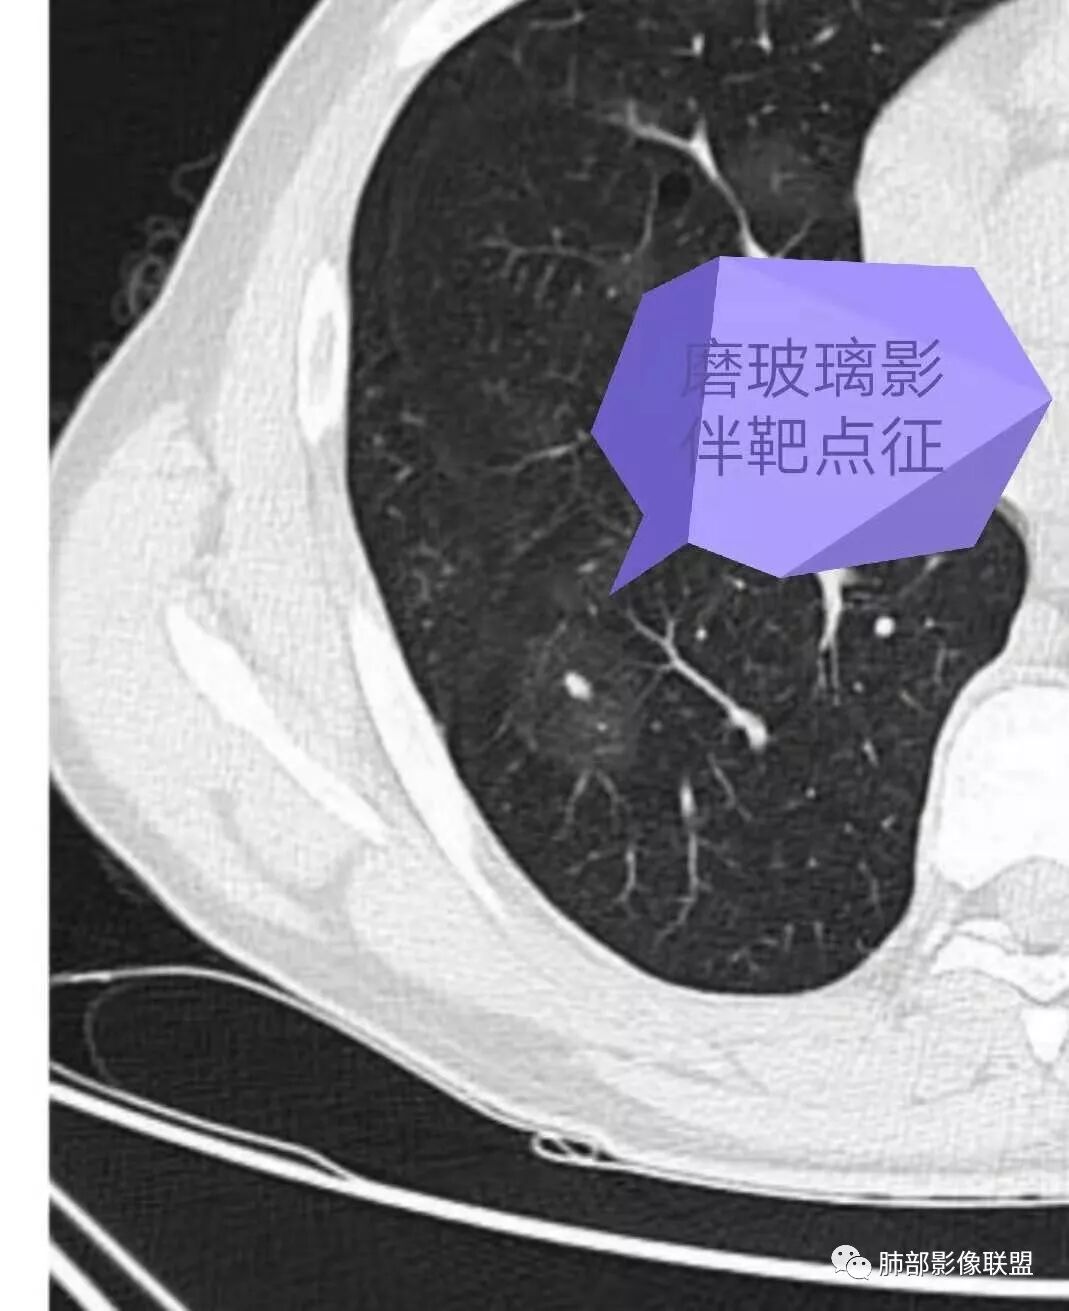

1.双肺多发磨玻璃结节影,边界可分辨,病灶中央都可见一实性密度小结节影,注意不是钙化。这些病灶形态及密度是如此相似,宛如身着厚厚一层晕影蜉蝣深海之中,称之为“点晕征”。

注意:多发、点、厚晕

2.肺部“点晕征”病灶更多见于血管肉瘤、上皮样血管内皮细胞瘤、肺动脉肉瘤等等。

47岁男性,咳血痰左肩背痛1月余,左肩胛骨破坏,破坏处及周边见软组织肿块,左肩胛区包块并皮肤破损,破损处无渗液、无脓不支持结核。两肺见多发磨玻璃影,沿血管走行,其内血管明显增粗,部分磨玻璃影内可见点状实性结节,呈点晕征,各磨玻璃影形态密度基本一致,提示同一来源,支气管未见明显增厚扩张——不支持气道来源。小叶间隔无增厚及纵隔未见明显肿大淋巴结——感觉淋巴瘤可能性较小。胸腹部皮肤散在红斑。整体考虑左肩胛骨恶性肿瘤并两肺转移。

影像特征:左肩胛骨区巨大软组织肿块,可见肩胛骨骨质吸收破坏,肺内多发随机分布结节,和血管关系密切,周围模糊GGO影,结合病史,左肩肿块考虑原发肿瘤,肺内考虑血行性转移伴出血;

点是转移结节,晕是出血吧?